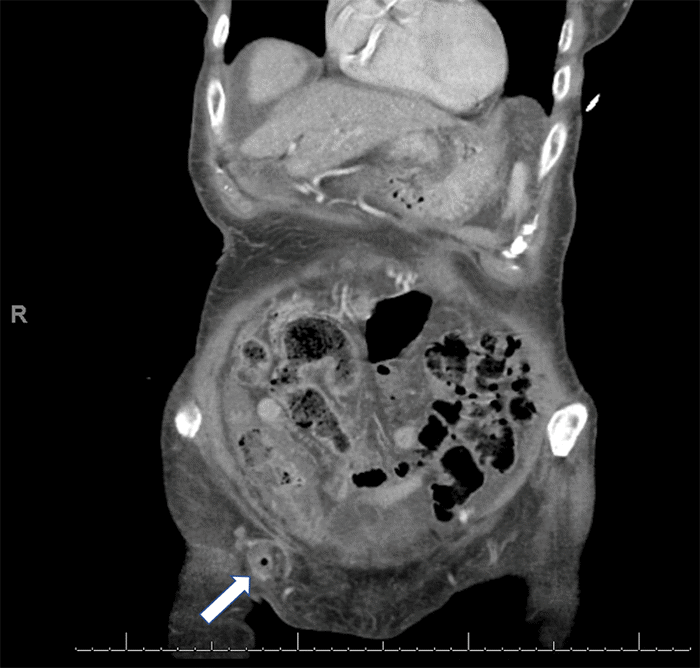

Figure 1. Coronal Abdominal CT Scan Demonstrating De Garengeot Hernia. Published with Permission

Fat and fluid content within the hernia sac are evident in the right lower quadrant (arrow). The appendix is visualized within the hernia sac, closely approximating the inguinal ligament